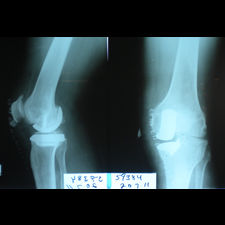

A 58 year old, male patient presented with a history of left knee pain and loss of function over 4 years.

On clinical and radiological examination, he was assessed as having Medial Compartment Osteoarthritis. A uni-compartmental knee replacement was recommended and performed in June 2011. Patient has gone onto complete recovery with a satisfactory clinical outcome. She returned to independent function, six weeks after the surgery and now has an pain-free existence with full function in the right knee after two months.